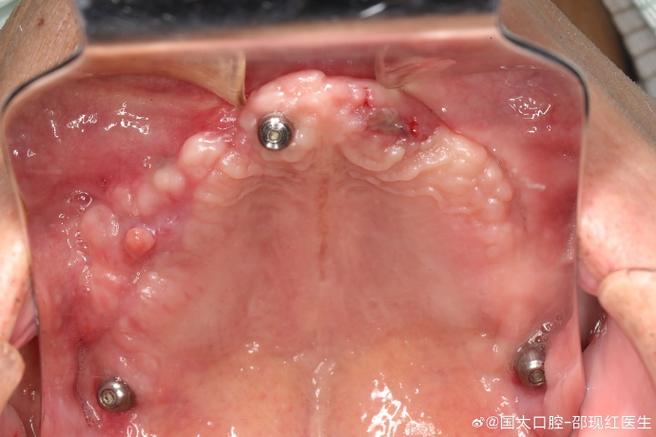

- 上颌窦是位于上颌骨内的一个空腔(鼻窦之一),其底部(底壁)通常与上颌后牙(前磨牙和磨牙)的牙根非常接近,有时甚至牙根会突入窦腔内。

- 当这些牙齿因各种原因(如严重龋坏、根尖周炎、外伤等)拔除后,如果拔牙窝的上颌窦底壁骨质非常薄或缺失,或者拔牙操作不当损伤了上颌窦黏膜,就可能导致口腔和上颌窦之间形成异常的通道,这就是“上颌窦漏”或“上颌窦口腔瘘”。

- 种植体直接进入上颌窦: 如果在漏口未修复的情况下强行种植,种植体尖端很可能直接穿透薄骨壁或漏口进入上颌窦腔,这是非常严重的并发症。

- 骨量不足: 上颌窦漏通常意味着上颌窦底部的骨量严重不足,种植体需要足够的骨组织来提供初始稳定性和长期的骨结合(Osseointegration),没有足够的骨,种植体无法成功植入或无法长期稳定。